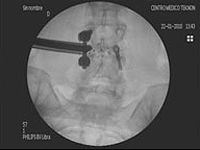

Implante percutáneo a través de cuatro incisiones de sólo 1 cm, sin cirugía abierta.